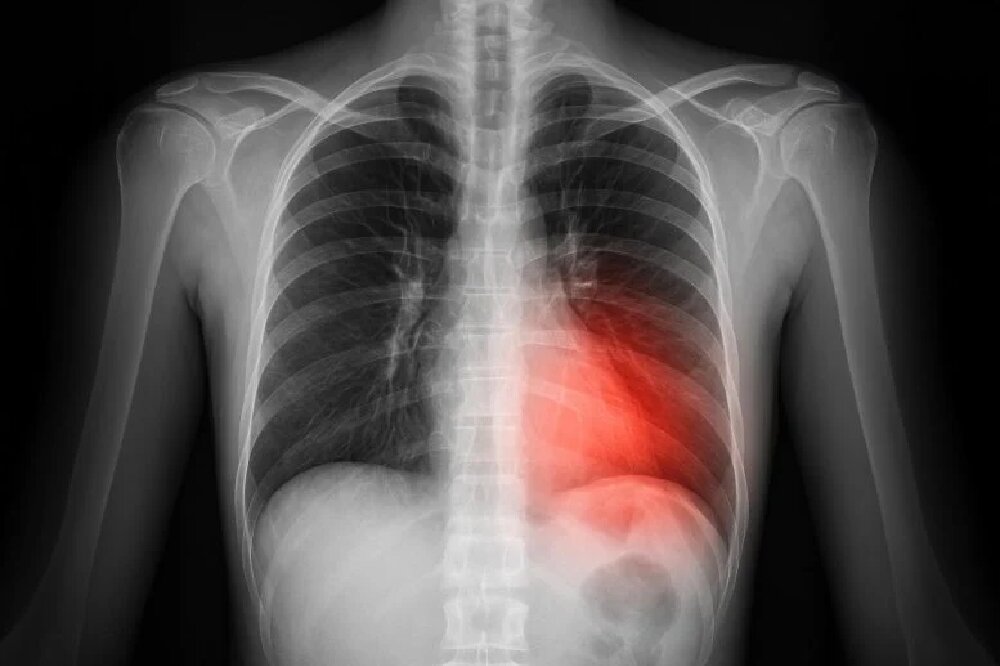

فروپاشی ریه توسط ژنی پنهان در بدن انسان!

ژنی پنهان در بدن انسان که زمانی تصور میشد بسیار نادر است، اکنون ممکن است بهطور شگفتآوری رایج باشد و بتواند بیصدا موجب بروز مشکلات جدی برای سلامت انسان شود.